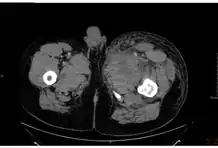

| A skin lesion with black eschar characteristic of anthrax | |